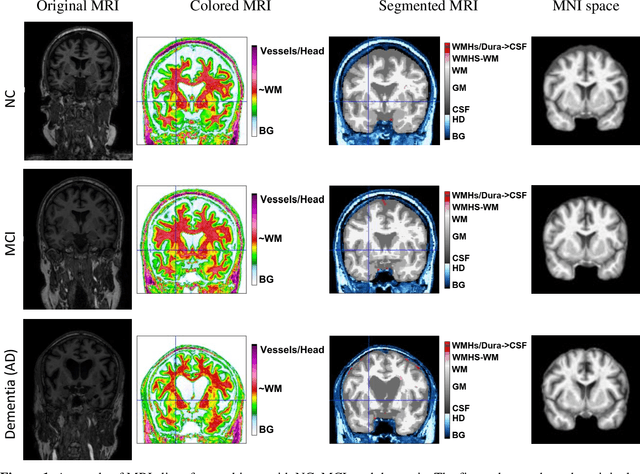

Abstract:Alzheimer's disease (AD) is a neurodegenerative disorder affecting millions worldwide, necessitating early and accurate diagnosis for optimal patient management. In recent years, advancements in deep learning have shown remarkable potential in medical image analysis. Methods In this study, we present "ViTranZheimer," an AD diagnosis approach which leverages video vision transformers to analyze 3D brain MRI data. By treating the 3D MRI volumes as videos, we exploit the temporal dependencies between slices to capture intricate structural relationships. The video vision transformer's self-attention mechanisms enable the model to learn long-range dependencies and identify subtle patterns that may indicate AD progression. Our proposed deep learning framework seeks to enhance the accuracy and sensitivity of AD diagnosis, empowering clinicians with a tool for early detection and intervention. We validate the performance of the video vision transformer using the ADNI dataset and conduct comparative analyses with other relevant models. Results The proposed ViTranZheimer model is compared with two hybrid models, CNN-BiLSTM and ViT-BiLSTM. CNN-BiLSTM is the combination of a convolutional neural network (CNN) and a bidirectional long-short-term memory network (BiLSTM), while ViT-BiLSTM is the combination of a vision transformer (ViT) with BiLSTM. The accuracy levels achieved in the ViTranZheimer, CNN-BiLSTM, and ViT-BiLSTM models are 98.6%, 96.479%, and 97.465%, respectively. ViTranZheimer demonstrated the highest accuracy at 98.6%, outperforming other models in this evaluation metric, indicating its superior performance in this specific evaluation metric. Conclusion This research advances the understanding of applying deep learning techniques in neuroimaging and Alzheimer's disease research, paving the way for earlier and less invasive clinical diagnosis.